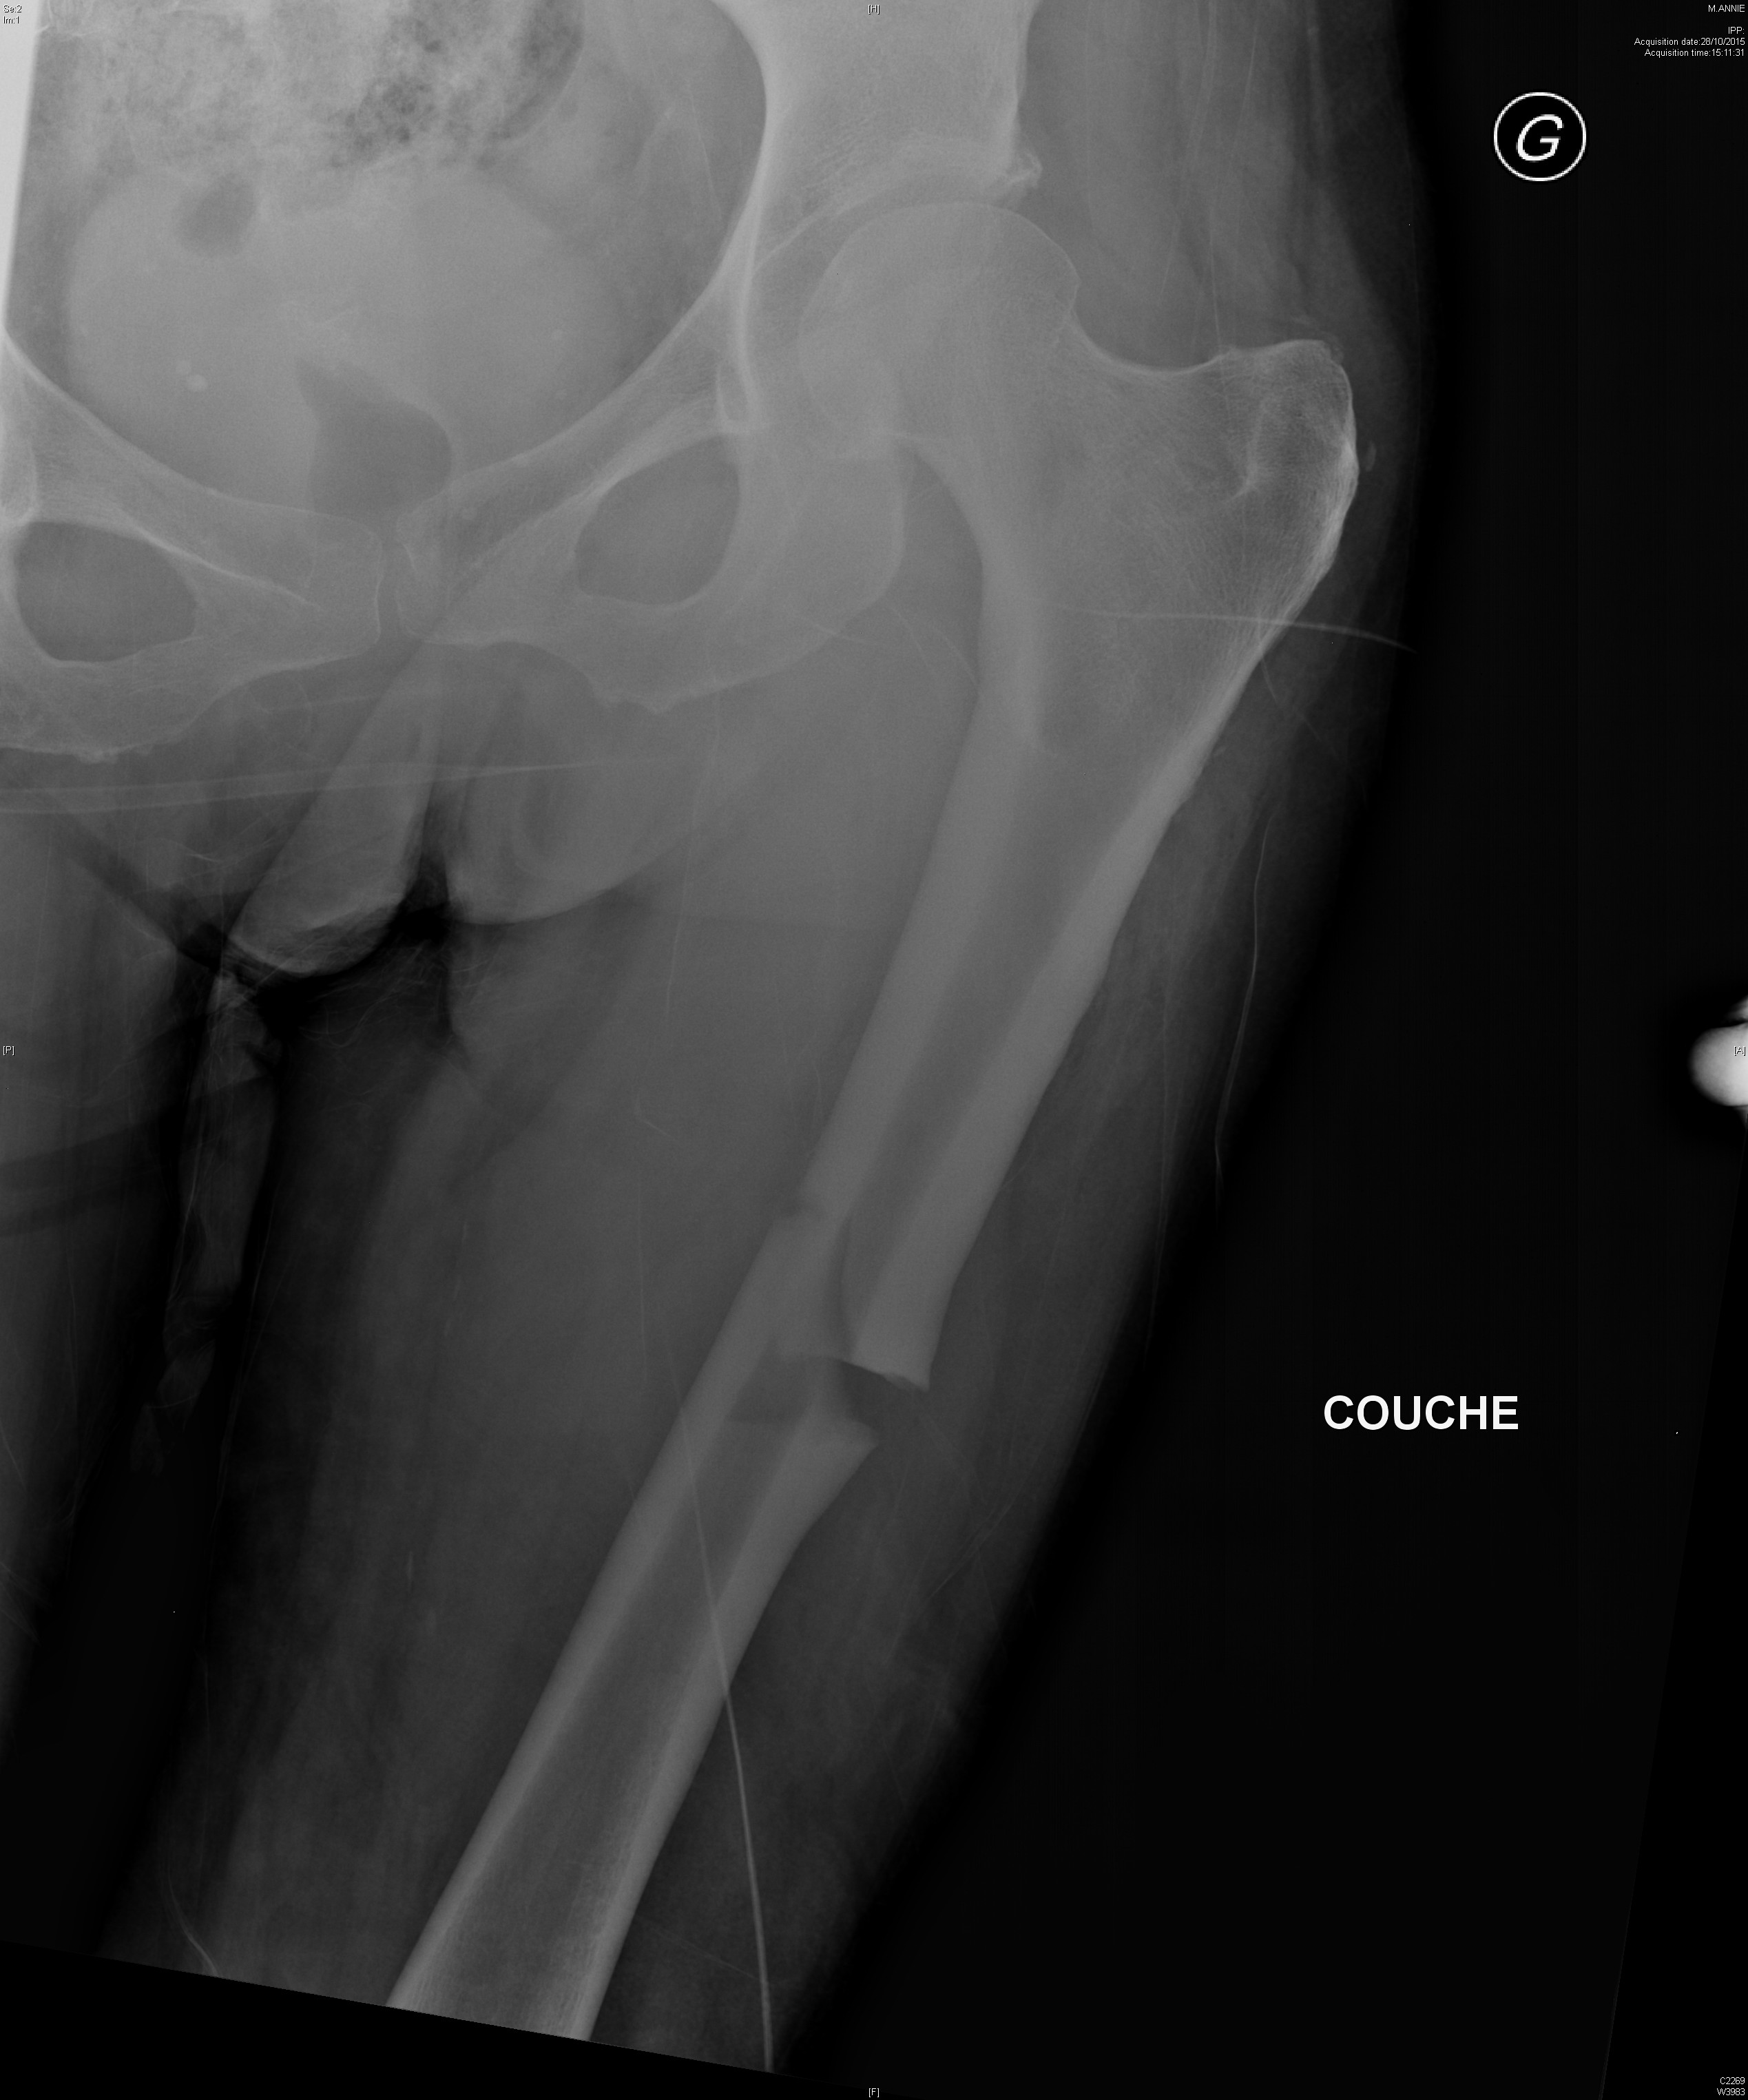

Coxite rapidement destructrice avec ostéonecrose chez une patiente traitée dans le cadre d'un syndrome des anti-synthétases

Dysplasie fibreuse du fémur gauche dans un contexte de dysplasie fibreuse polyostotique

Radiographie retrouvant une dysplasie acétabulaire bilatérale ainsi qu'une lésion de dysplasie fibreuse du col fémoral droit chez une jeune fille